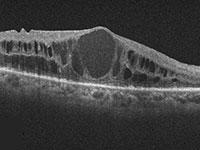

● 光干渉断層血管撮影機器(OCTA)

網膜疾患や緑内障の診断に用いられてきた光干渉断層計(OCT:optical coherence tomography)は、非侵襲的に網膜の断面を描出する機器でとして広く普及しています。当院では、8年前からOCTを導入し、網膜疾患と緑内障の診断と治療に活用してきました。

今回、新たにOCTに血管撮影の機能が付いた光干渉断層血管撮影機器(OCTA: OCT angiography、アンギオOCT)を導入いたしました。

これまで、網膜の血管を描出するには造影剤が必要でした。しかし、この最新の機器を用いることにより、網膜やその下にある脈絡膜血管を、造影剤を用いずに短時間で血管撮影できるようになりました。造影剤を用いた検査(蛍光眼底撮影)は、手間のかかる検査であるだけではなく、副作用のリスクもあるため、実施できない患者様もおられました。 OCTAは、これまでの造影剤を用いた検査の問題点を解決してくれる画期的な機器です。

OCTAを用いることで、これまでの網膜の断層撮影に加えて

① 加齢黄斑変性の脈絡膜新生血管の描出や治療効果の確認

パキコロイド新生血管症(PNV)に対するマイクロパルス閾値下レーザー治療を行い、網膜下液が吸収された症例。